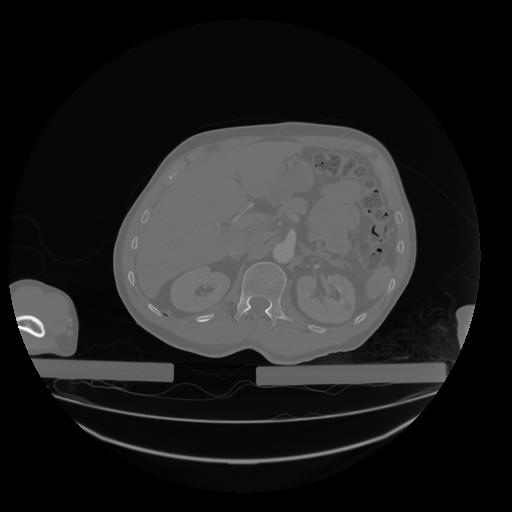

28 CUERPO,CE,Vol,2.0,CUERPO,,